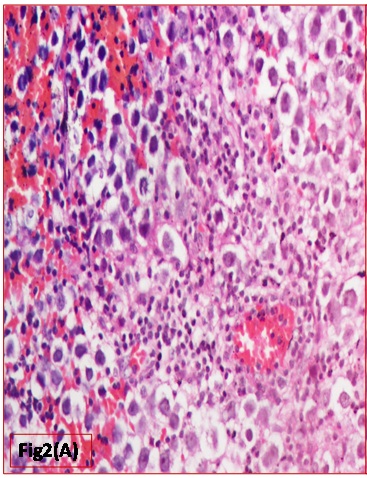

Histopathological evaluation showed a tumour with monomorphic large germ cells with enlarged centrally located vesicular nucleus, prominent nucleolus and moderate clear cytoplasm arranged in sheets, divided into lobules by fibrous septa with lymphocytic infiltrates and stromal hemorrhage; foam cells were also noted [Table/Fig-2a,b]. Also seen were immature glands lined by columnar cells with hyperchromatic nuclei and subnuclear- vacuolation surrounded by atypical spindle shaped stromal cells and foci of immature cartilage [Table/Fig-3]. Large areas of sinusoidal vascular channels surrounded by cytotrophoblasts and syncytiotrophoblasts were seen suggestive of choriocarcinoma [Table/Fig-4a,b].

Monomorphic large germ cells representing Germinoma (H&E: 200X)

Atypical mitotic figure seen (H&E: 400X)